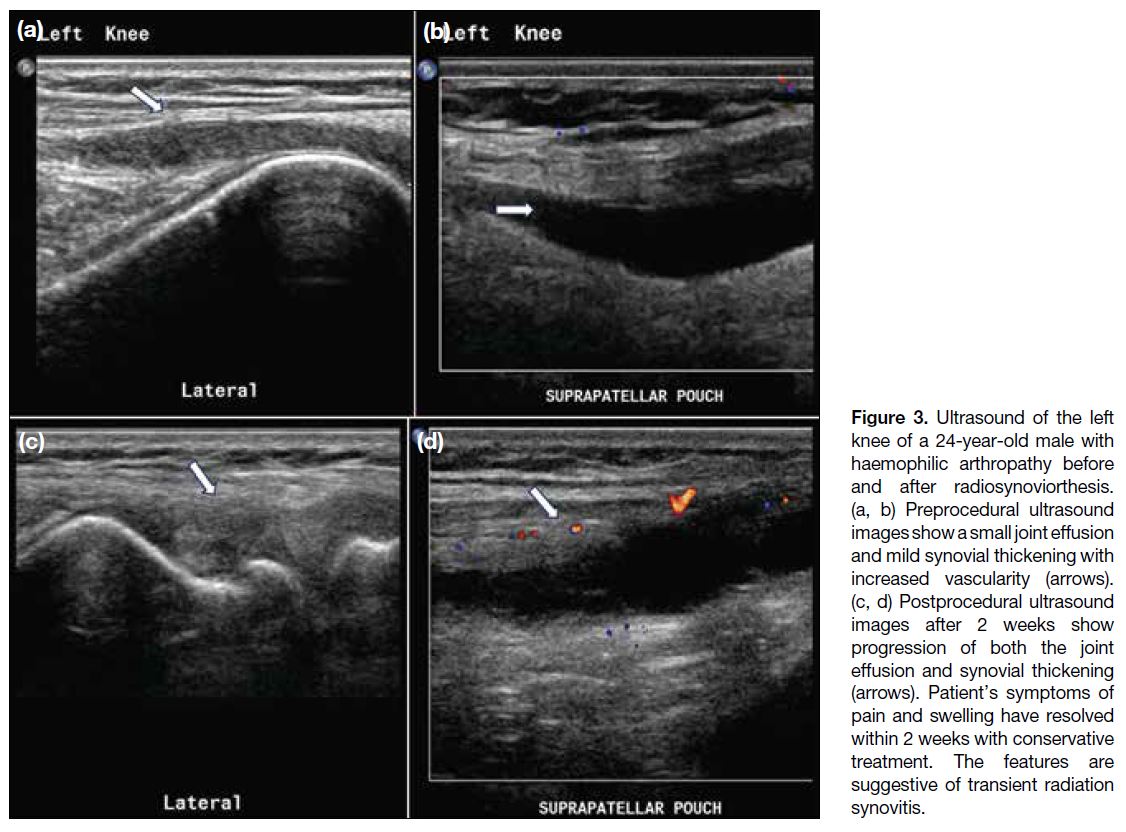

Two (4%) joints developed transient radiation

synovitis (95% CI=0.5%-15%), characterised by pain

and swelling shortly after the procedure. Ultrasound

confirmed increased joint effusion and synovitis (Figure 3). These symptoms resolved within 2 weeks following

conservative treatment with ice packs and nonsteroidal

anti-inflammatory drugs.

Figure 3. Ultrasound of the left

knee of a 24-year-old male with

haemophilic arthropathy before

and after radiosynoviorthesis.

(a, b) Preprocedural ultrasound

images show a small joint effusion

and mild synovial thickening with

increased vascularity (arrows).

(c, d) Postprocedural ultrasound

images after 2 weeks show

progression of both the joint

effusion and synovial thickening

(arrows). Patient’s symptoms of

pain and swelling have resolved

within 2 weeks with conservative

treatment. The features are

suggestive of transient radiation

synovitis.